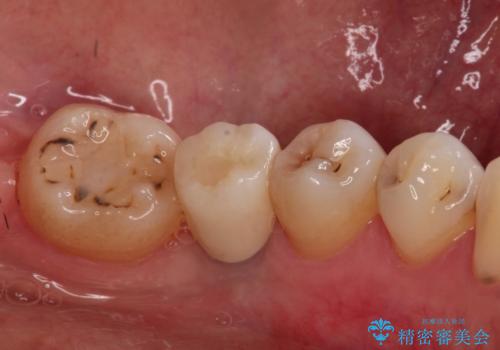

歯並びの改善とインプラントでのかみ合わせの回復 インプラント・セラミック・矯正全顎治療

- 歯医者が怖くて悪い歯をそのままにしてしまった、悪いところを治したいとのことで来院されました。

虫歯の歯や、歯を抜いてしまったところをそのまま放置していたことにより、歯並びも悪くなっていました。

矯正をはじめ、根の治療・インプラント・セラミックによる全体治療を提案させていただき、治療をしていくこととなりました。